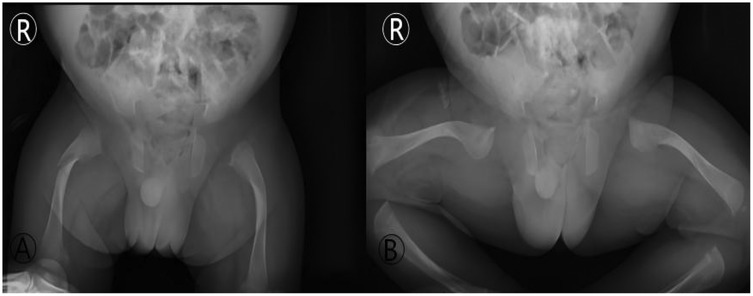

Background: Osteogenesis Imperfecta (OI) poses a unique challenge in pediatric trauma and critical care, where the fragility of bone intersects with life-threatening systemic complications, such as neonatal respiratory failure. The early postnatal period is particularly precarious, demanding a delicate balance between life support and fracture prevention. Case Presentation: A 9-day-old male neonate with prenatally diagnosed COL1A2 (c.1459G>A, p.Gly487Arg) mutation was admitted to our NICU for respiratory distress and pneumonia. He was the progeny of a father with OI, delivered via cesarean section at 34 weeks due to fetal skeletal deformities. Management and Outcomes: A proactive, multidisciplinary team (MDT) protocol was immediately implemented, focusing on non-invasive respiratory support, meticulous handling to prevent iatrogenic injury, and optimized nutrition. This approach successfully resolved his respiratory failure without any new fractures during the NICU stay. However, on the 16th day post-discharge, the infant sustained a spontaneous fracture of the right proximal femur. This was managed conservatively with a Pavlik harness. Follow-up revealed rapid callus formation by day 52 and complete union by day 136, showcasing the characteristic hyperplastic healing pattern of OI. Conclusion: This case underscores that a coordinated MDT approach is vital for stabilizing critically ill neonates with OI. The occurrence of a fracture shortly after discharge highlights the transition to home care as a period of extreme vulnerability. Empowering families with comprehensive education and ensuring continuity of care are as crucial as in-hospital management for improving long-term outcomes in these fragile infants.